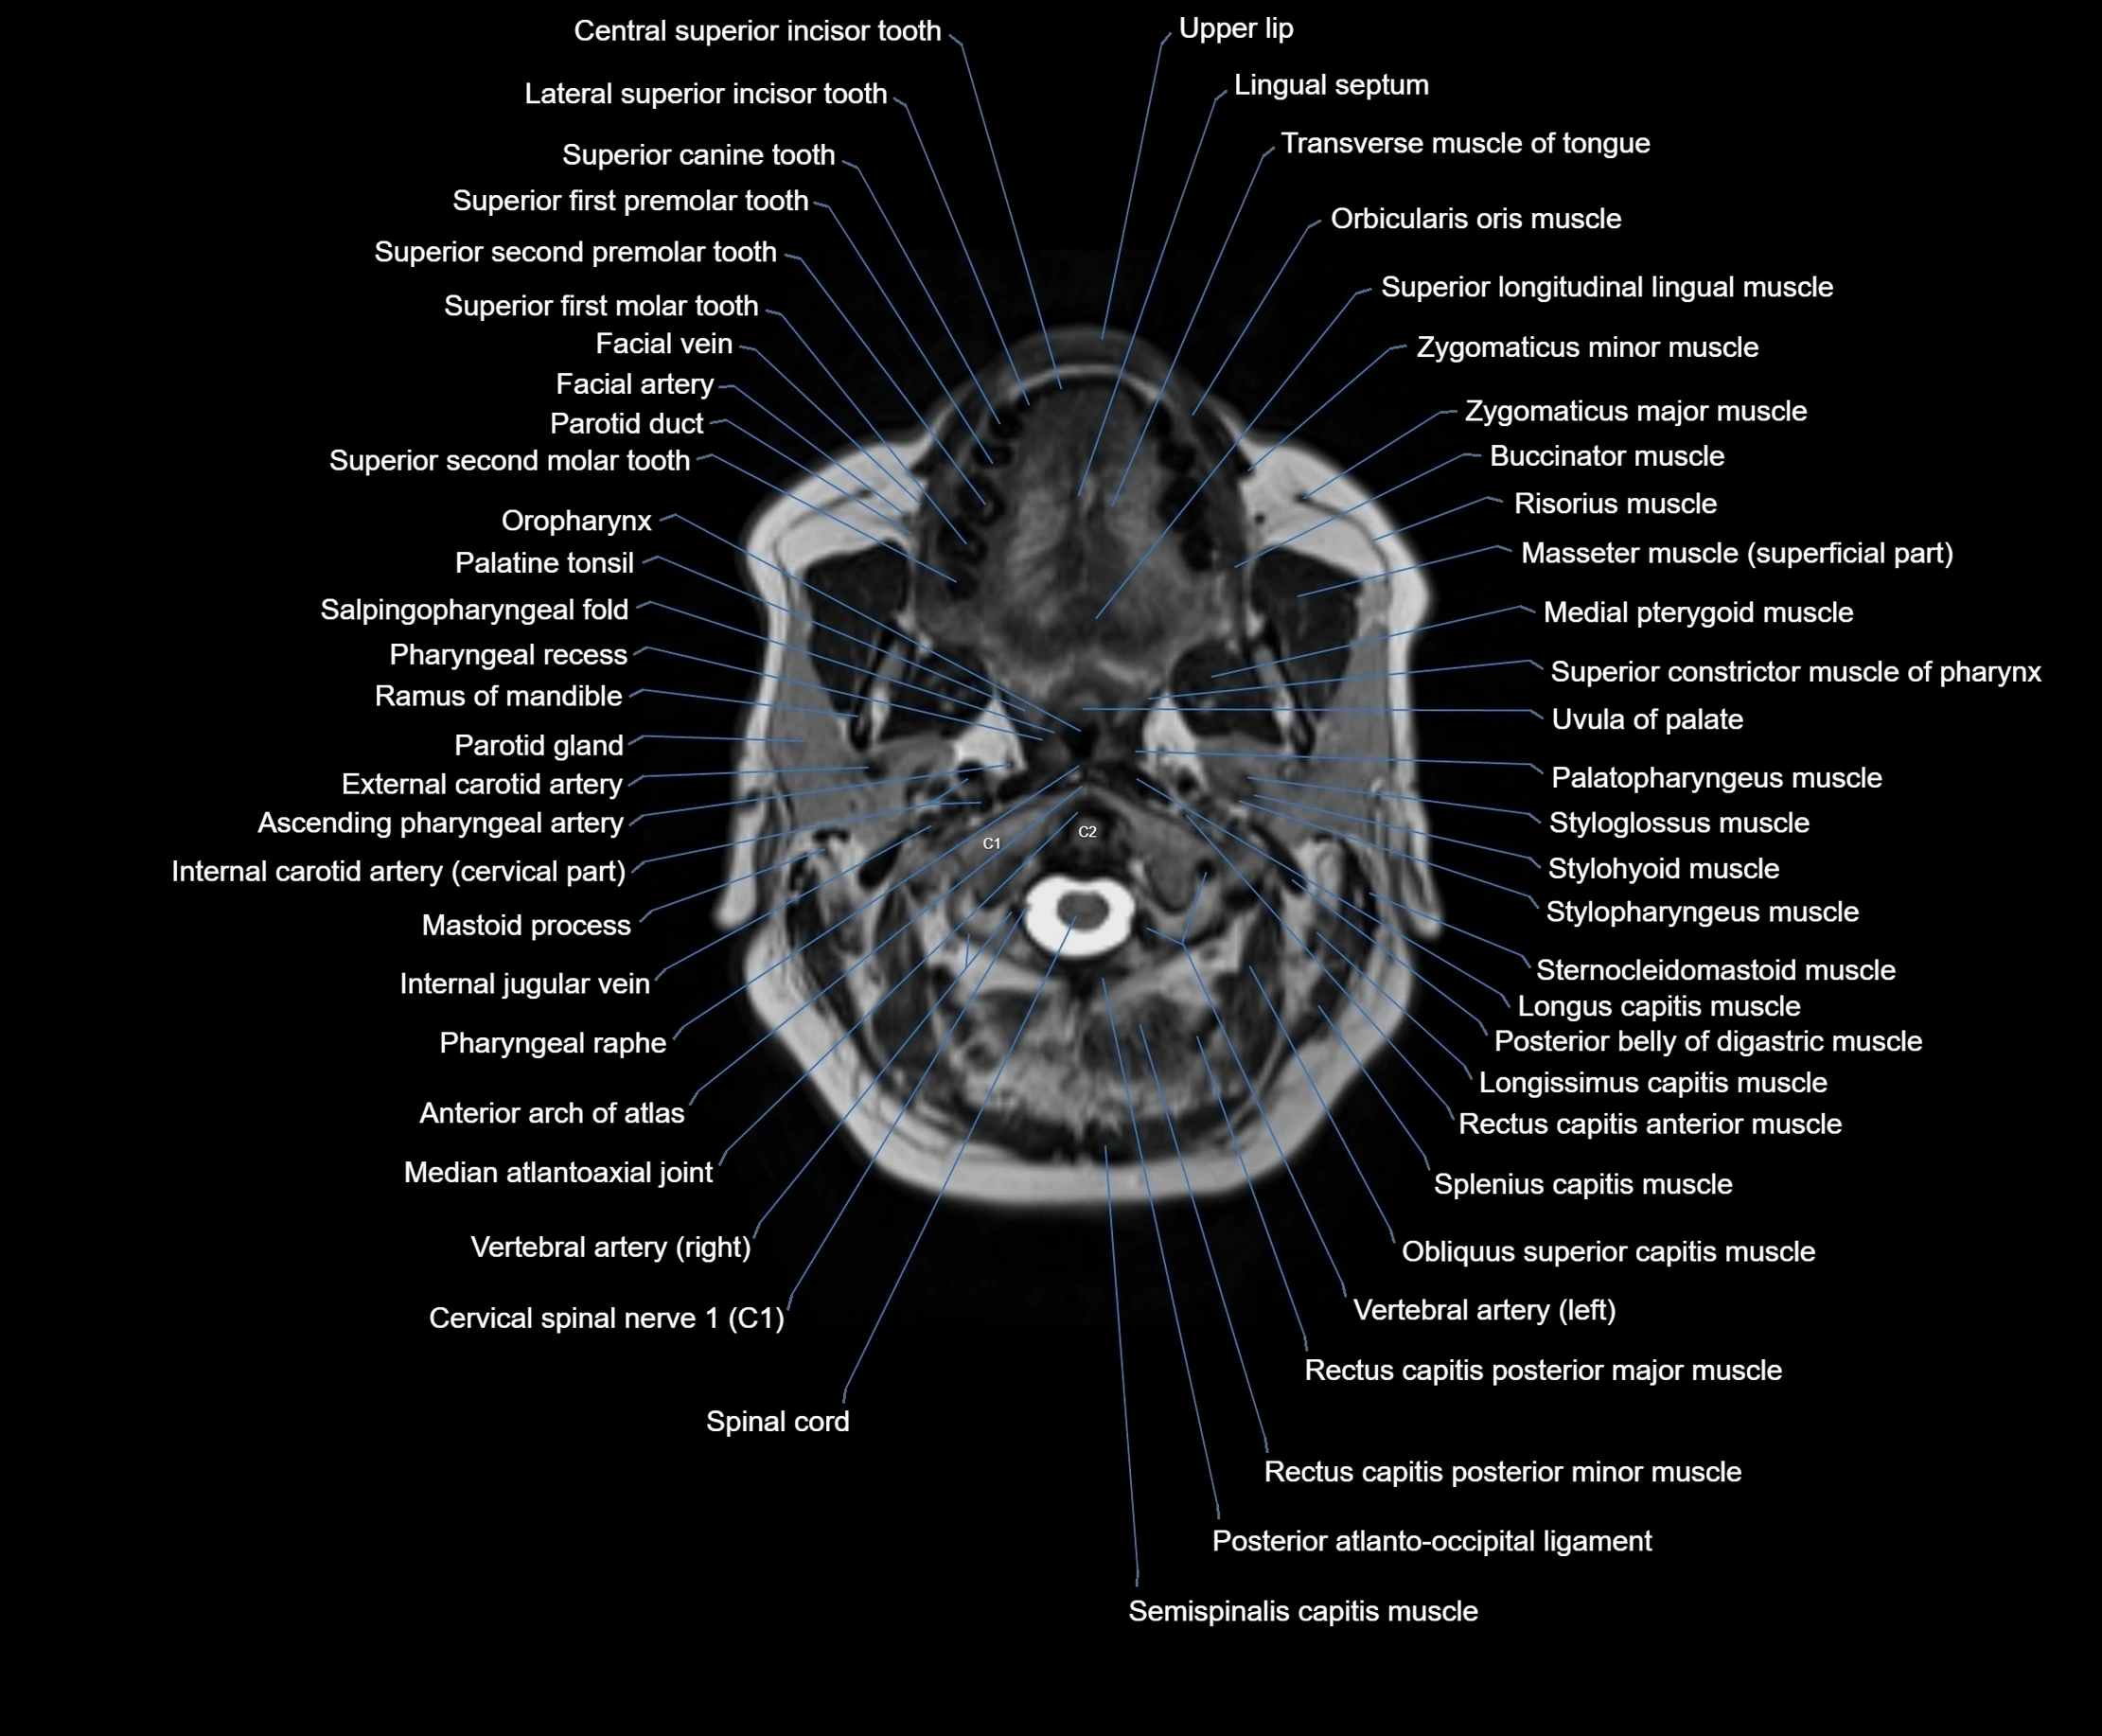

MRI images